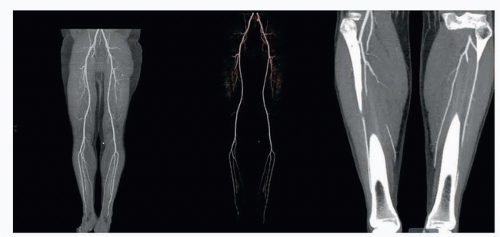

Knowledge of the ankle’s vascular anatomy is essential for limb salvage. The distal lower extremity’s arterial supply is primarily supplied by three vessels: posterior tibial (PT), anterior tibial (AT), and peroneal.

The AT artery branches from the popliteal artery, and its course across the ankle is shown (FIG 1, left).

The PT and peroneal arteries originate from the tibioperoneal trunk, and their courses across the ankle are shown (FIG 1, right).

Computed tomographic angiography (CTA) (FIG 3) can obtain vascular information valuable for flap planning and assessing the recipient site without risk of complications associated with arterial puncture of the groin.

Selective preoperative CTA may be considered in patients who have lost peripheral pulses, had a neurological deficit secondary to the injury, or of a compound fracture that has undergone reduction and external or internal fixation.2